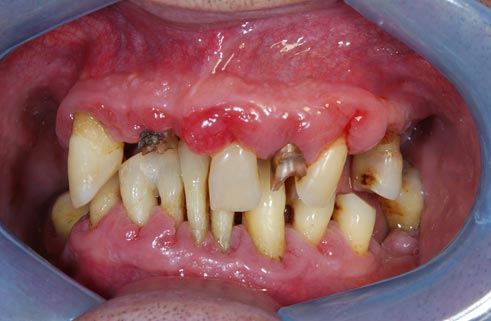

Riabilitazione implanto - protesica superiore ed inferiore in un paziente di 84 anni

I denti irrecuperabili dell'arcata superiore ed inferiore del paziente di anni 65 sono stati sostituiti da 10 impianti, cioè protesi radicolari endo-ossee che sostengono le protesi fisse superiore ed inferiore.